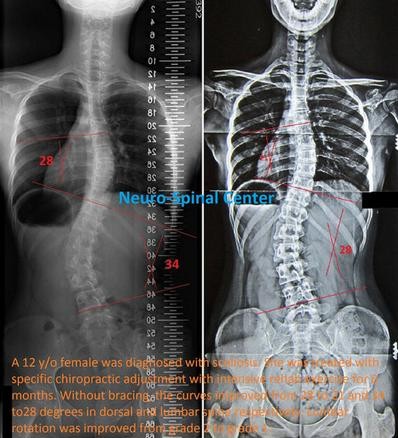

case1: